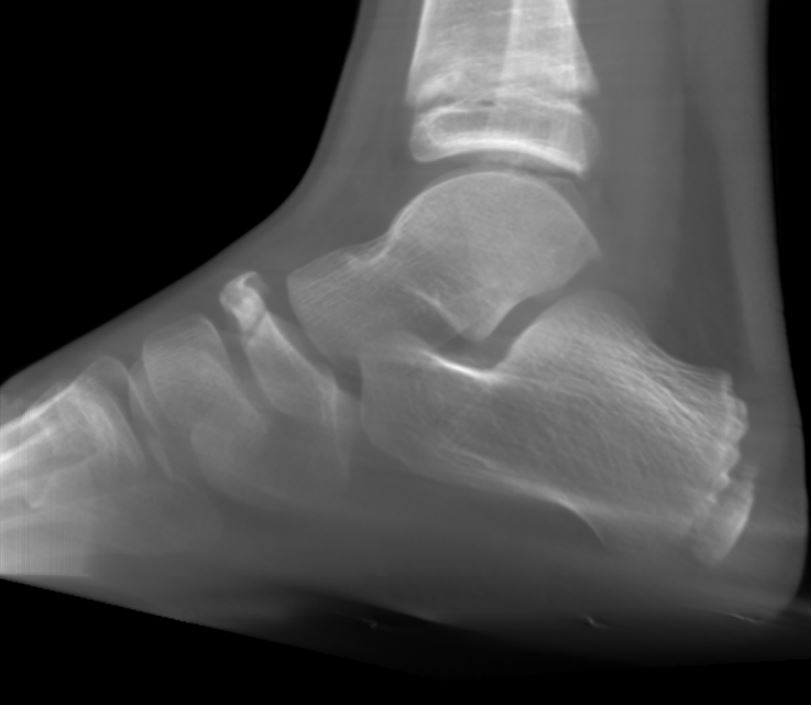

Kindlicher Rückfuß DVT

• DVT / Röntgen